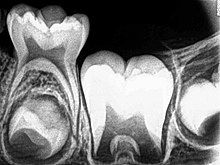

年轻恒牙有以下特点:①根基不牢,容易松动;②根管粗大,根管壁薄;③根尖孔大,呈喇叭口状。这样的牙齿,注定存在一定的弱点。

图源:维基百科